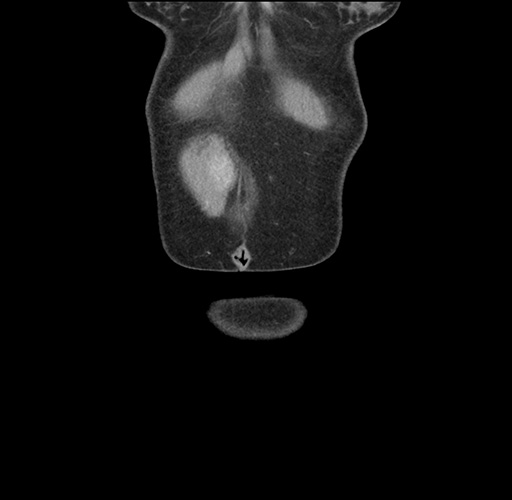

Imaging Analysis

Look through the patient's CT scan to identify any areas of concern for the necessary procedure.

Based on your CT findings, which issue(s) would give reason for "planned slowing down moment(s)" in this case?